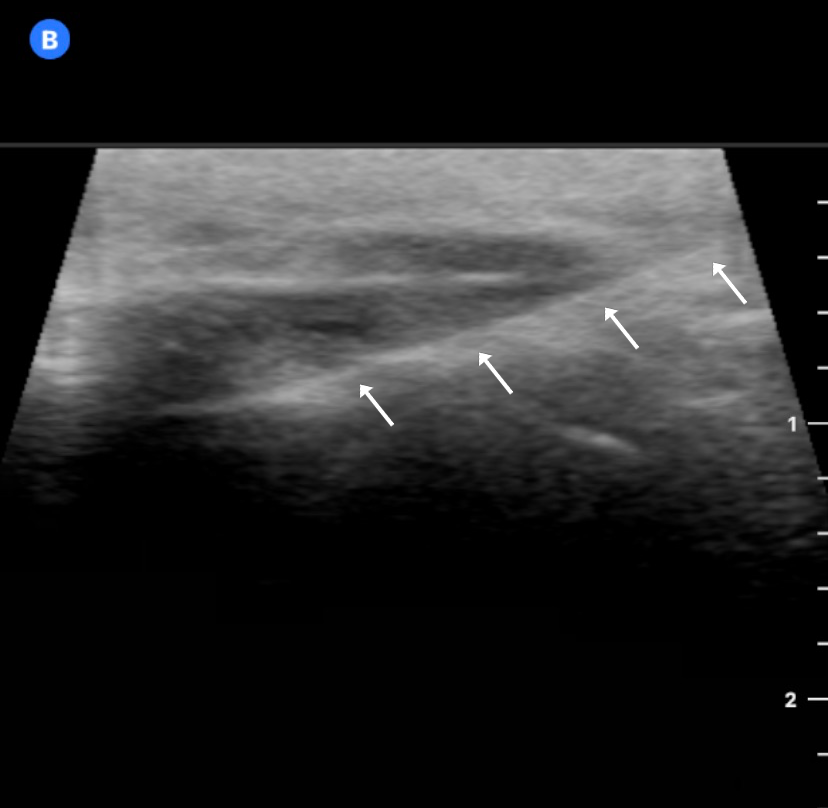

Ultrasound-guided punctures may approach the target (joints, vessels or nerves) from a position perpendicular or parallel to the US beam, referred to as ‘out-of-plane’ and ‘in-plane’, respectively (Figure 4). The in-plane approach enables the operator to visualize the needle shaft and tip, as it is directed toward the target, but it requires skill and may result in a false sense of security, despite having been demonstrated to result in faster and more accurate performance. On the other hand, the out-of-plane technique is more difficult and relies on tissue movement or fluid localization rather than strict needle visibility to confirm its position.46 In the TMJ US-guided injections using the out-of-plane approach, the correct position of the needle is achieved by extending and narrowing the joint space by the infiltration and aspiration of fluid, respectively.19 Champs et al. validated a longitudinal US-guided in-plane approach for TMJ IAI, in which the needle is inserted at an angle of 30°, with the US probe in the preauricular region, approx. 1 cm in front of the tragus, parallel to the mandibular ramus and perpendicular to the zygomatic arch.21 This technique proposes a direct visualization of the needle all the way to the joint with great precision and provides noticeably higher accuracy during puncture.21 Most clinical and cadaveric studies use the coronal route of scanning and in-plane needle insertion (Figure 5),9, 10, 11, 12, 14, 17, 18, 19, 20, 21 whereas other reports did not report these technical details.13, 15, 16